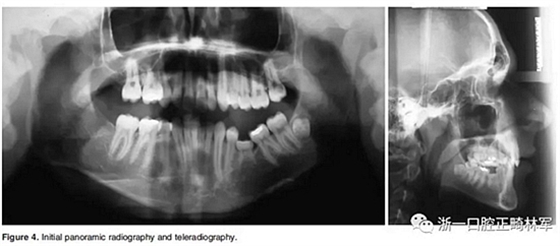

4.影像檢查:右上前磨牙和左下第二前磨牙缺失(Figure 4)。在另一名牙齒矯正醫(yī)師治療4年后,患者在19歲時被轉(zhuǎn)診給我們。他的咬合特征與他的初始狀態(tài)非常相似(Figure 5)